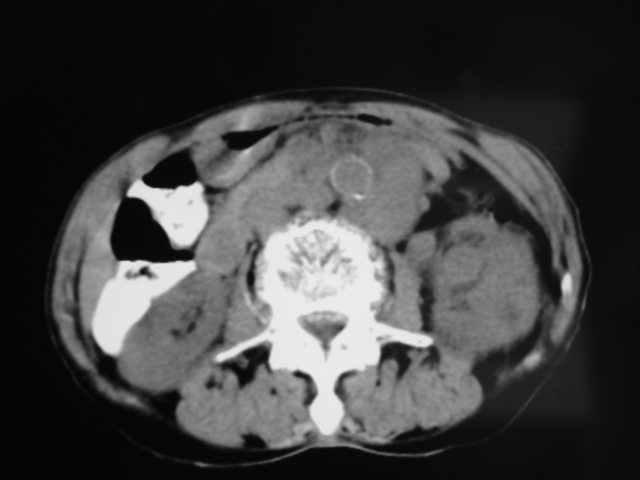

同事奶奶,73岁,腹痛一年,夜晚较重,潜血+++,拒绝增强,考虑左肾ca并腹膜后转移;请各位老师帮忙看看,谢谢!

左肾癌侵及输尿管上段,腹膜后多发淋巴结转移,脾脏钙化灶。至于潜血+++,要考虑消化道病变,本次ct片肠腔未见明显异常。

1)考虑左肾癌侵犯肾盂并腹膜后淋巴结转移。2)脾脏钙化灶。

查查一胸部,不除外肺癌伴左侧肾上腺,腹膜后淋巴结及左肾转移.